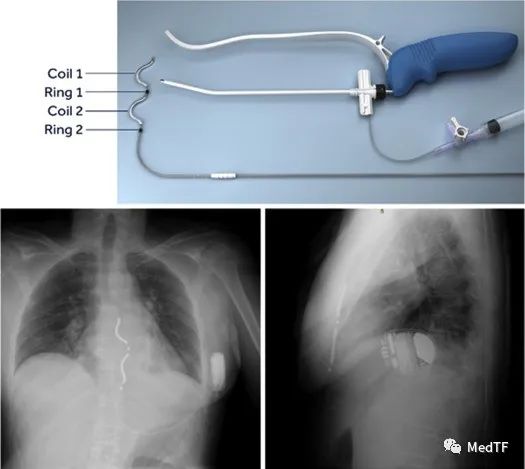

Aurora EV-ICD除颤器和导线组成,其的大小与传统的除颤器(33立方厘米 )相当,一般植入到左腋下下方(左腋中部)。该除颤器除了功能与传统 ICD相似(除颤、抗心动过速起搏 (ATP) 等),就连形状和寿命方面与传统 ICD 也相似。该除颤器可提供高达40J的电流(比波科小一半),并配有设计用于胸骨后治疗的传感和起搏电路。

Aurora EV-ICD导线为ε形,具有2个起搏/传感电极和2个除颤线圈段(每个4厘米),为了除颤目的将其绑在一起以形成一个8厘米的整体除颤线圈。Aurora EV-ICD中有3个传感和3个起搏向量可用。感测矢量包括2个环形电极之间的近场矢量和从每个环形电极到ICD装置的2个远场感测矢量。起搏向量包括环到环向量、线圈到线圈向量以及从远端环到近端线圈段的向量。